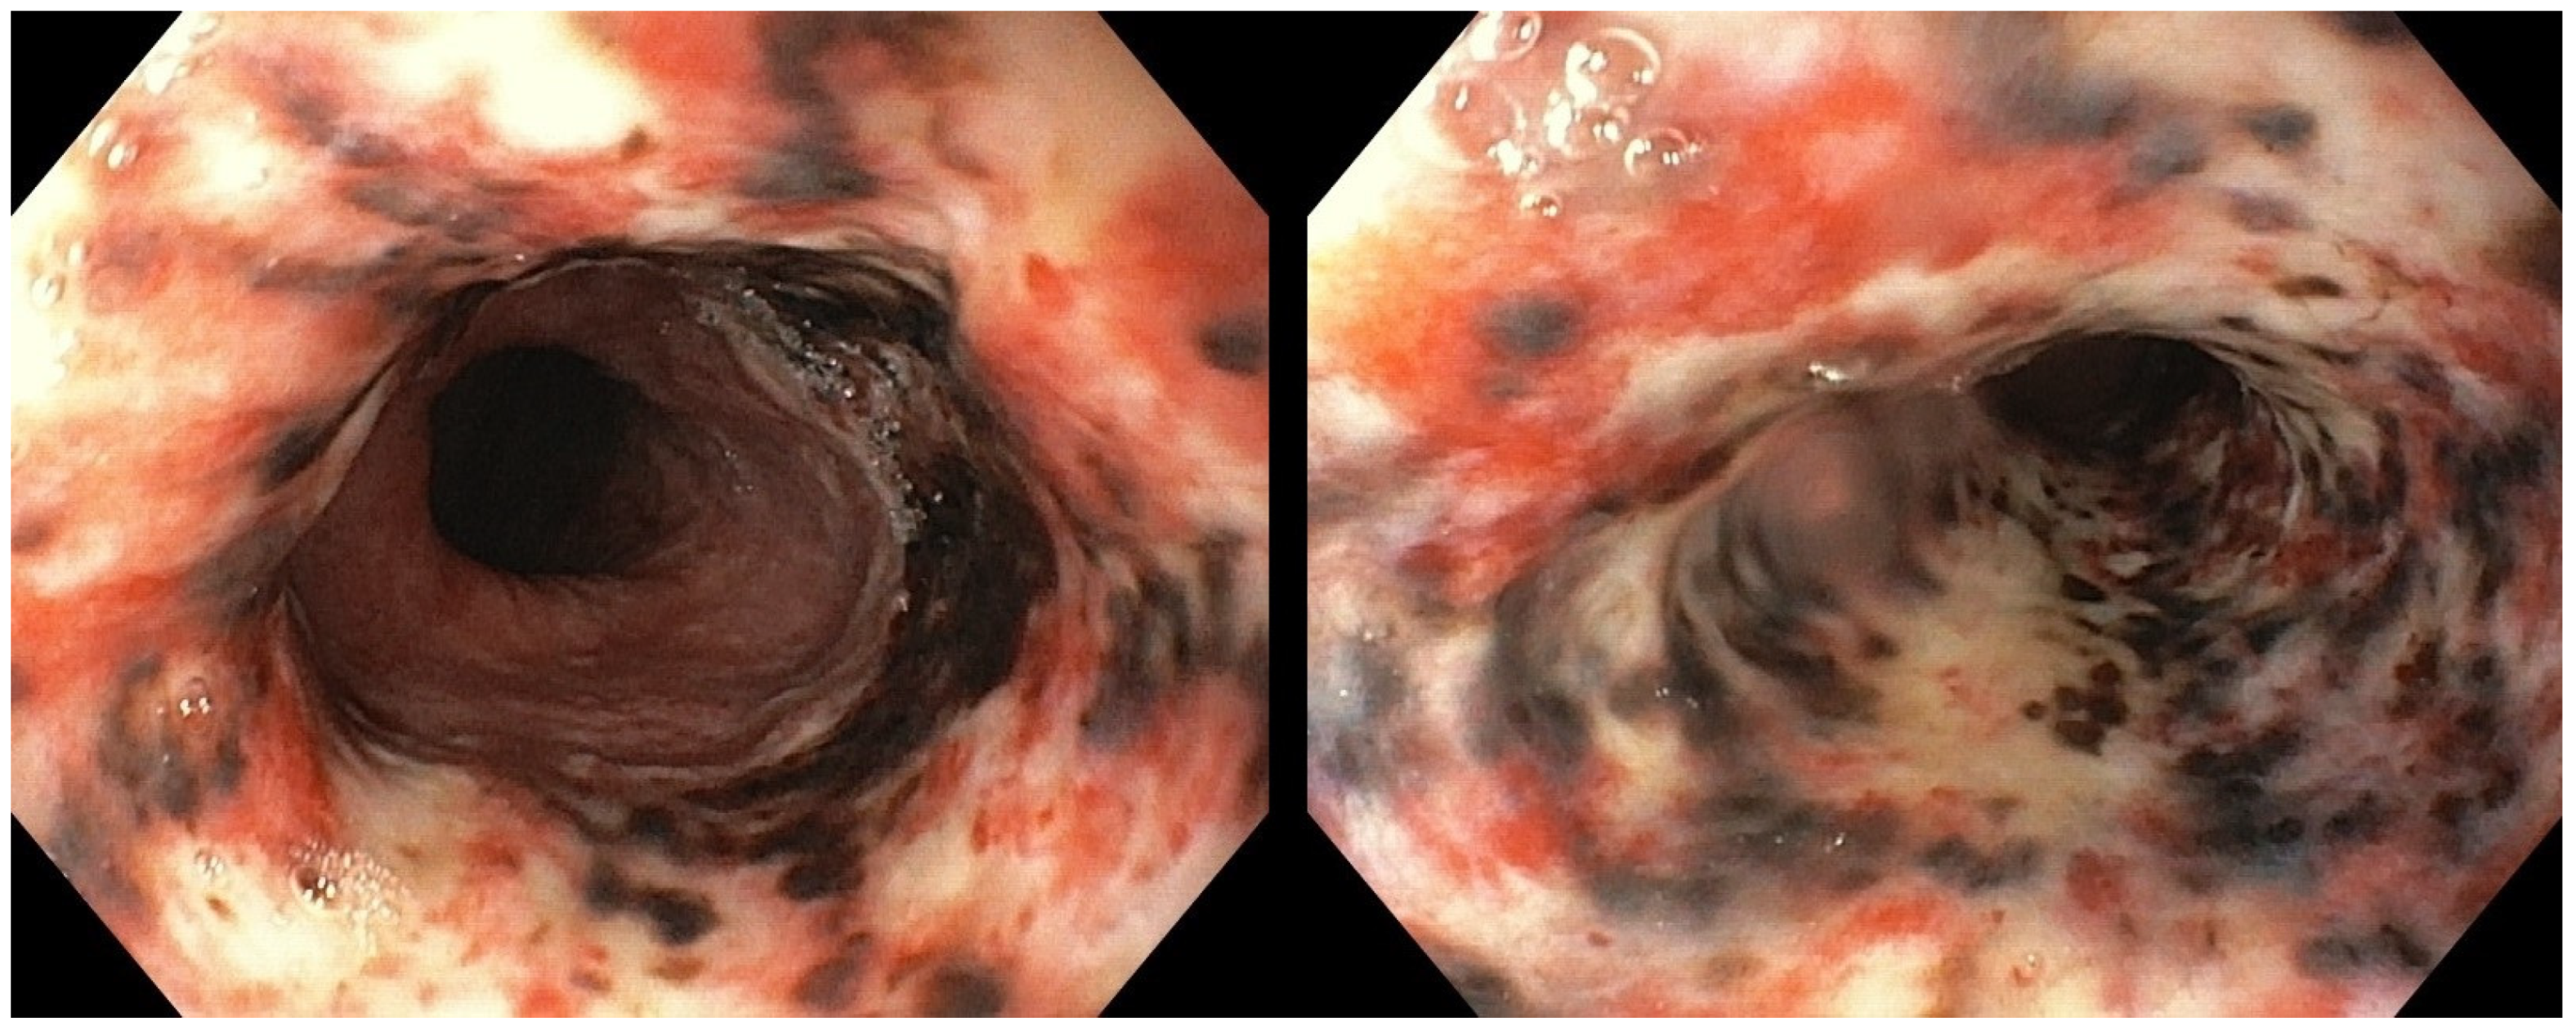

The patient was admitted to our Bleeding Unit. After the hemodynamic stabilization, an urgent esophagogastroduodenoscopy (EGD) under monitored anesthesia care was carried out. The endoscopic examination showed diffuse, circumferential, black-colored, friable mucosa at the middle and the distal esophagus, in the absence of signs of active bleeding. Gastric mucosa was spared (Figure 2). Esophageal biopsies were not taken at this time due to concern about a possible perforation.

Figure 2.

Urgent esophagogastroduodenoscopy showing diffusely black-colored mucosa at the level of the middle and the distal esophagus, abruptly ending at the gastro-esophageal junction.